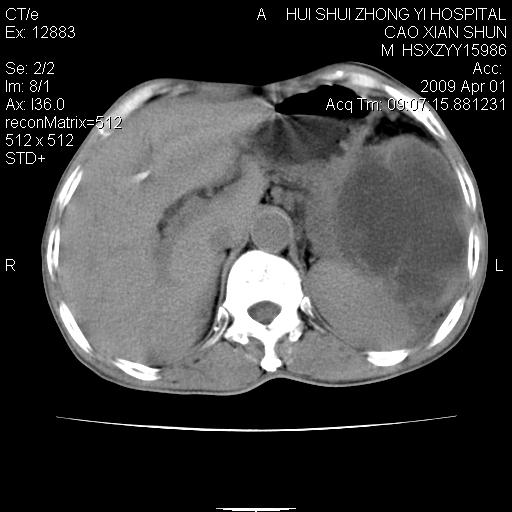

以下是引用随光逐影在2009-4-1 14:23:00的发言:[br]肝、脾多发低密度占位性病变,性质待定(不排除转移瘤可能);建议行进一步检查。

以下是引用liaoqiang在2009-4-1 15:53:00的发言:[br]考虑脾脏肿瘤或胰尾部肿瘤伴肝转移。建议增强。

以下是引用ydx_74在2009-4-1 15:18:00的发言:[br]肝、脾多发低密度占位性病变,考虑转移瘤或淋巴瘤